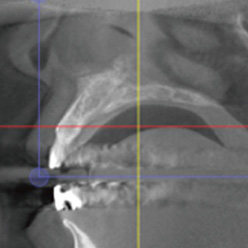

STEP1

CT촬영 + 구강스캔

이미지 정합